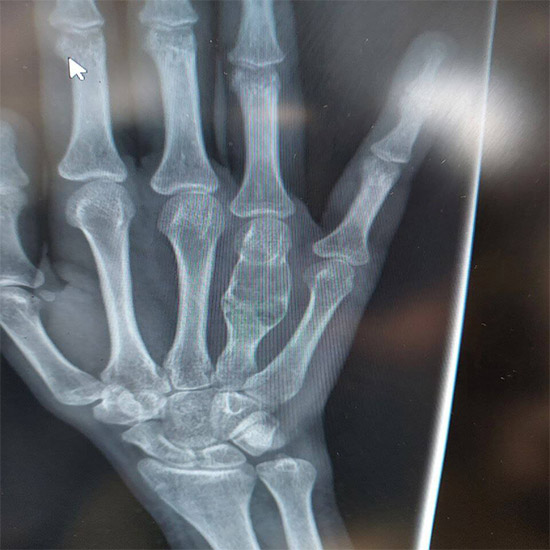

بخشی از نمونه کارها

نمونه کارهای قبل و بعد